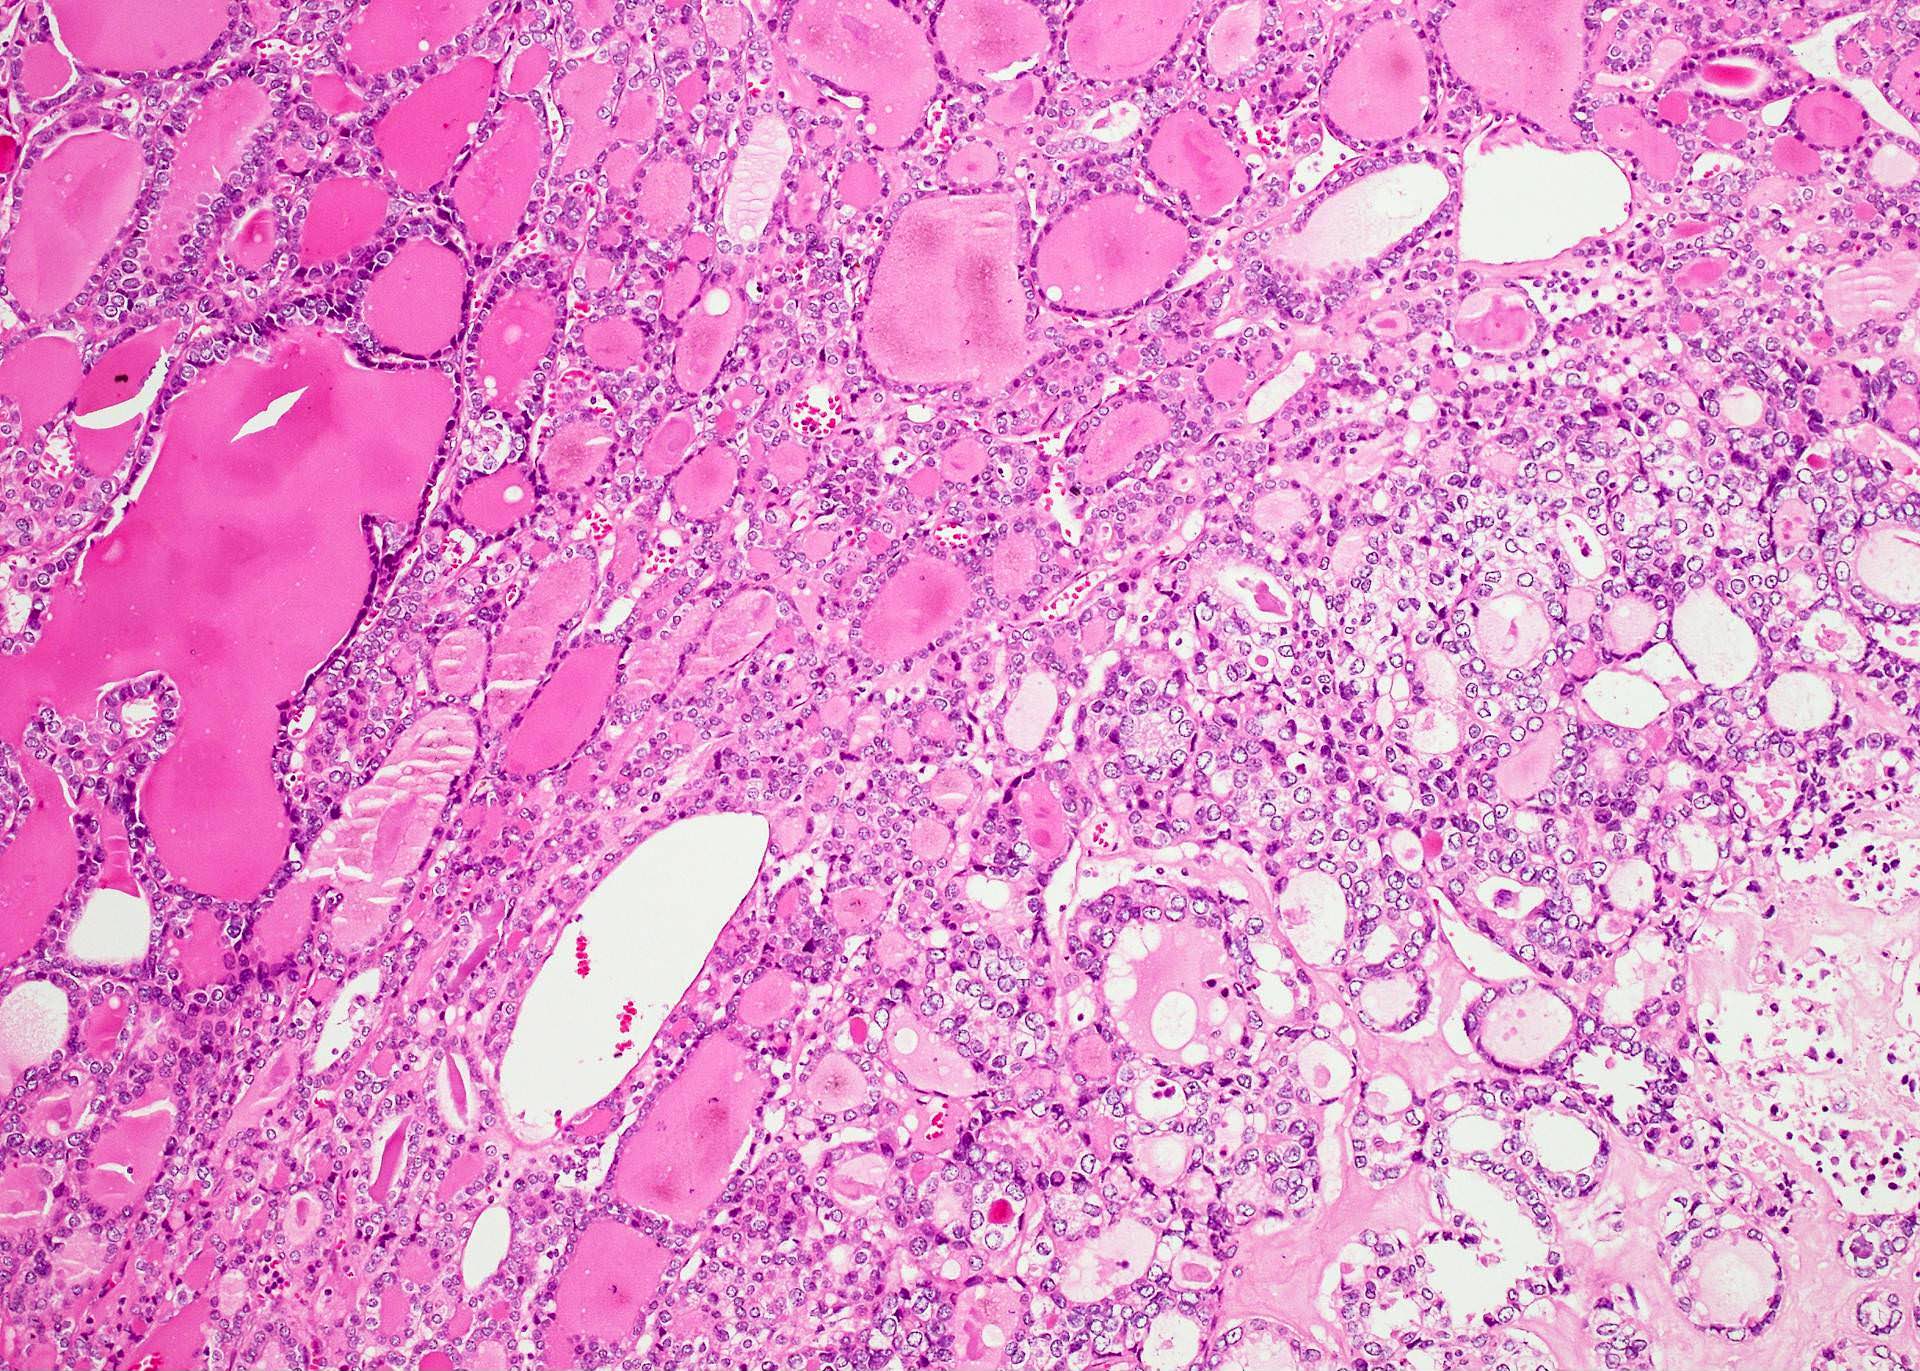

Microscopic (histologic) description

- Architecturally and cytologically different from surrounding gland

- Compression signs in surrounding thyroid tissue

- Encapsulated; thin or moderately thick capsule

- Architectural patterns (can be seen in any combination)

- Macrofollicular (colloid): large follicles, flattened epithelium, abundant colloid

- Solid / trabecular (embryonal): minimal or no colloid

- Secondary changes: fibrosis, hyalinization, hemorrhage, hemosiderin deposition, edema, cystic degeneration, calcification, osseous or cartilaginous metaplasia

- Variants

- Hyperfunctioning adenoma (Plummer adenoma): tall columnar epithelium, papillary infoldings, vacuolated cytoplasm, watery colloid showing scalloping

- Follicular adenoma with papillary hyperplasia: cystically dilated follicles, intraluminal papillae

Microscopic (histologic) images

Contributed by Shipra Agarwal, M.D., Andrey Bychkov, M.D., Ph.D., Mark R. Wick, M.D., Asmaa Gaber Abdou, M.D. and AFIP

Patterns:

Atypical adenomas: